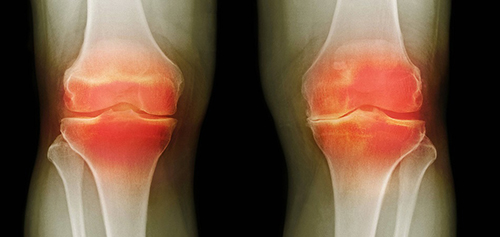

อาการปวดเป็นสัญญาณสำคัญที่บ่งชี้ว่ามีความผิดปกติในข้อ การแค่ทำให้หายปวดจะทำให้สภาพของข้อต่อแย่ลง กระบวนการเสื่อมสภาพจะเร็วขึ้น 3-5 เท่า ส่งผลให้เกิดการเปลี่ยนแปลงที่ย้อนกลับไม่ได้ สูญเสียการเคลื่อนไหวและนำไปสู่การพิการในที่สุด

เมื่อเกลือเหล่านี้เกาะอยู่บนพื้นผิวของข้อต่อ คราบเกลือเหล่านี้เหมือนกระดาษทรายที่ทำลายเนื้อเยื่อรอบโดยรอบ กระดูก และกระดูกอ่อน เมื่อผลึกโตขึ้น เกลือจะเริ่มทำลายเนื้อเยื่อของกล้ามเนื้อ เอ็น หลอดเลือด และเส้นเลือดฝอย ทำให้เกิดการอักเสบ ติดเชื้อ บวม ก่อให้เกิดการอักเสบและปวดอย่างรุนแรง

ในกรณีรุนแรง การสะสมเกลือจำนวนมากอาจทำให้กระดูกหักได้ง่ายเมื่อมีการเคลื่อนไหวอย่างกะทันหัน ส่งผลให้พิการและข้อต่อไม่สามารถเคลื่อนไหวได้